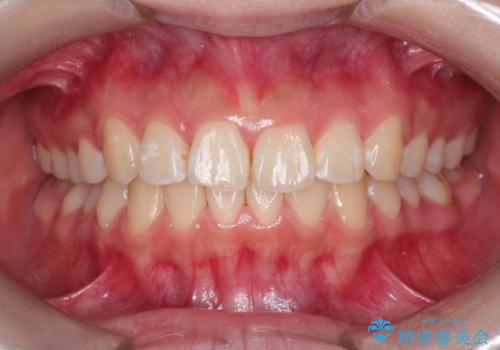

インビザラインによる出っ歯の非抜歯矯正

- 前歯が出ているのを主訴に来院されました。

上の前歯が前方に傾斜しており、上の前歯と下の前歯が接触していない状態でした。

上の奥歯を後方に移動させて、前歯を引っ込める計画としました。

しっかり使っていただけたので、スムーズに治療を終了することができました。